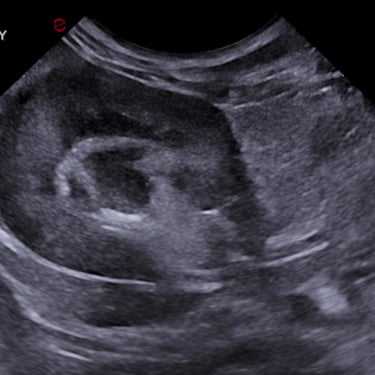

Practicing companion animal veterinary medicine in Simcoe County since 2012, Dr. Elyse is experienced in a variety of clinical settings from emergencies to chronic disease management and routine care.

Focusing on efficiency, workflow, and accuracy to provide actionable information to pet parents and veterinarians, while keeping patient wellbeing at the forefront.

Dr. Hauer has completed over 270 formal hours of continuing education in diagnostic abdominal and cardiac ultrasound from a variety of experts in the field, including a year-long immersive Advanced Imaging program through the Academy of Veterinary Imaging in Arlington, TX. She is a member of the International Veterinary Ultrasound Society.

Certificate of Completion in Advanced Imaging - Veterinary Ultrasound Education Program, Academy of Veterinary Imaging, Texas, 2015 (140 hours)

Sonopath SDEP Abdomen - (22 hours), 2023

Soft Tissue Level 3: Taking it Up a Notch - WAVE We Are Veterinary Education, 2025, (16 hours)